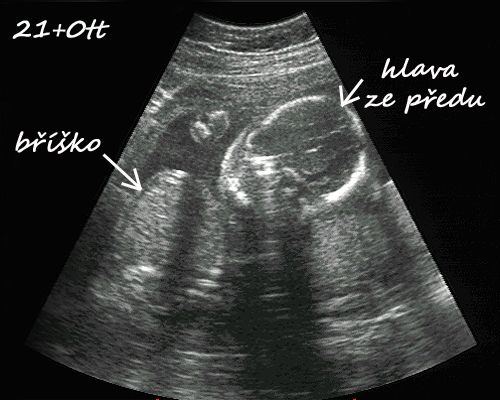

začínám 30tt-24.7. ultrazvuk, malá je snad zdravoučká a už ted je to naše láska 🙂 má odhadem v 29+0tt 1357g, rozměry bříška a hlavičky odpovídají stáří, ale nožička je o týden delší. No prý to bude dlouhán, což mě pobavilo, protože Nikolka měla při narození jen 43cm ( 36+3tt ). Tak uvidíme, jestli budou sestřičky každá úplně jiná 🙂